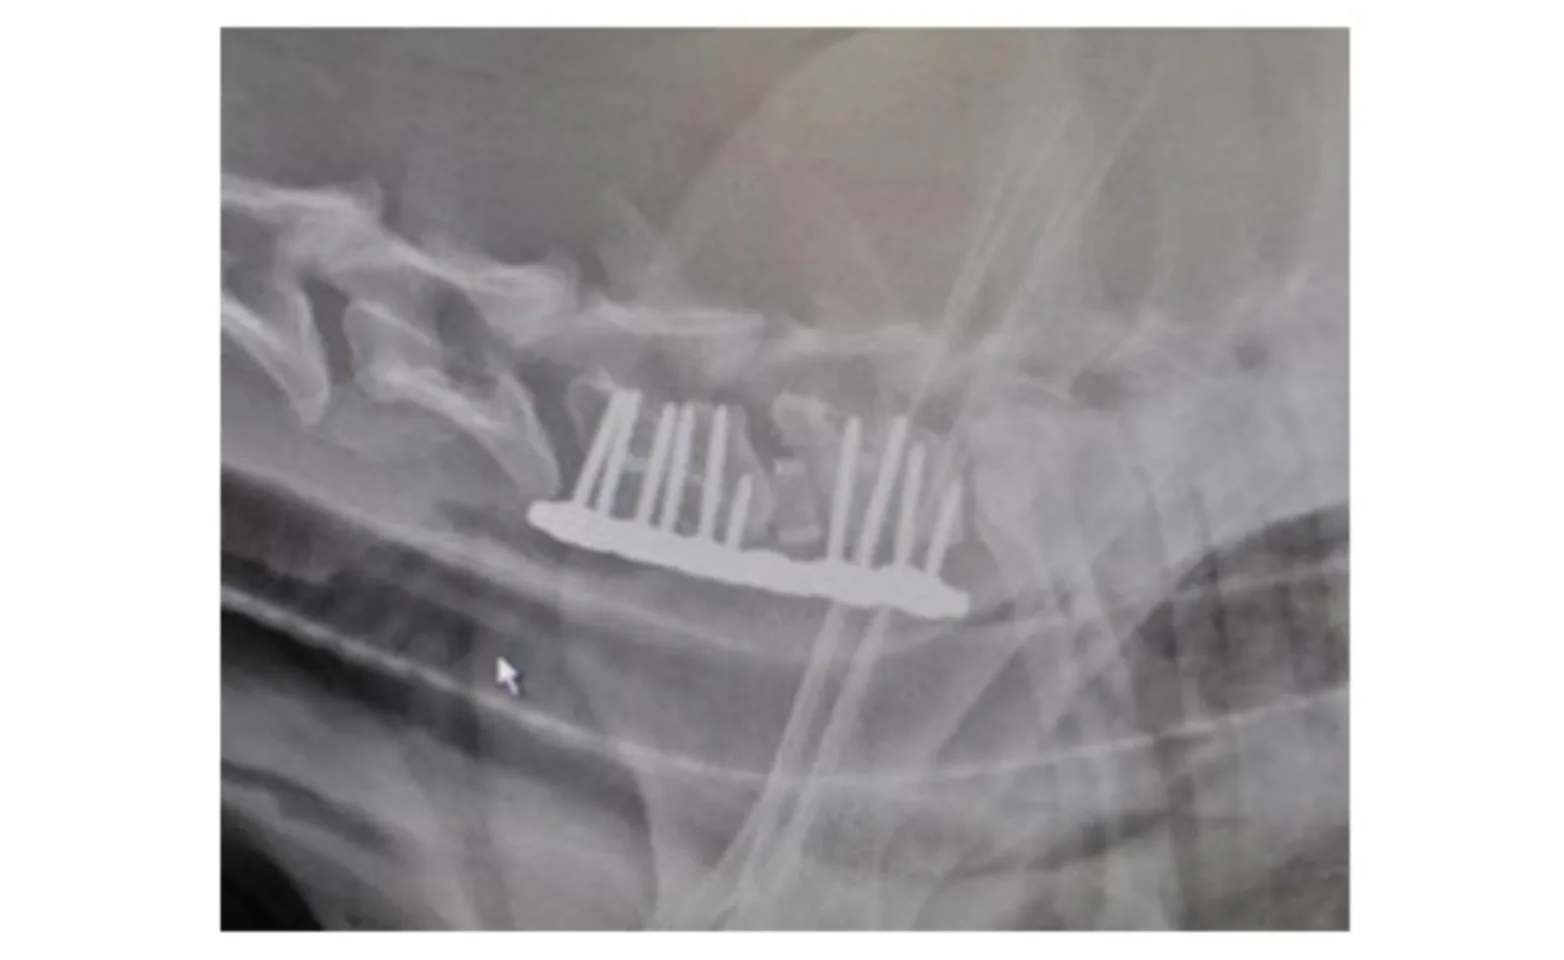

Surgical stabilization is the treatment of choice for the instability form of wobblers and generally carries a good to excellent prognosis. A partial ventral slot is performed in the central aspect of the two involved vertebrae and filled with cancellous bone. Intraoperative fluoroscopy is used to place 4 to 6 bone screws into the vertebral bodies. The screw heads are left protruding 1 - 1.5 cm ventral to the vertebra. Traction is applied across the affected vertebra resulting in flattening of the dorsal longitudinal ligament thereby relieving spinal cord compression. PMMA (bone cement) is placed so that it spans the two vertebrae and screw heads (Figure 2). This maintains the vertebrae in distracted position. The cancellous bone graft in the slot eventually causes the two vertebral bodies to fuse.